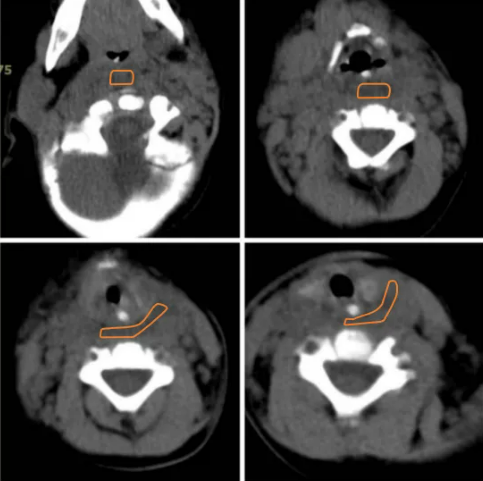

2021.12.28当地医院影像

2021.12.30治疗后影像